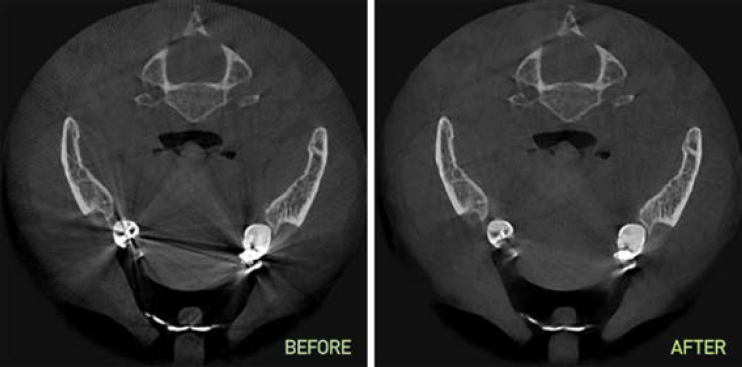

Технология исключения вторичного излучения металлов

SMARF (Smart Metal Artifacts Reduction Function). Обеспечивает превосходную визуализацию костных структур в условиях повышенного вторичного излучения от металлических конструкций в полости рта.